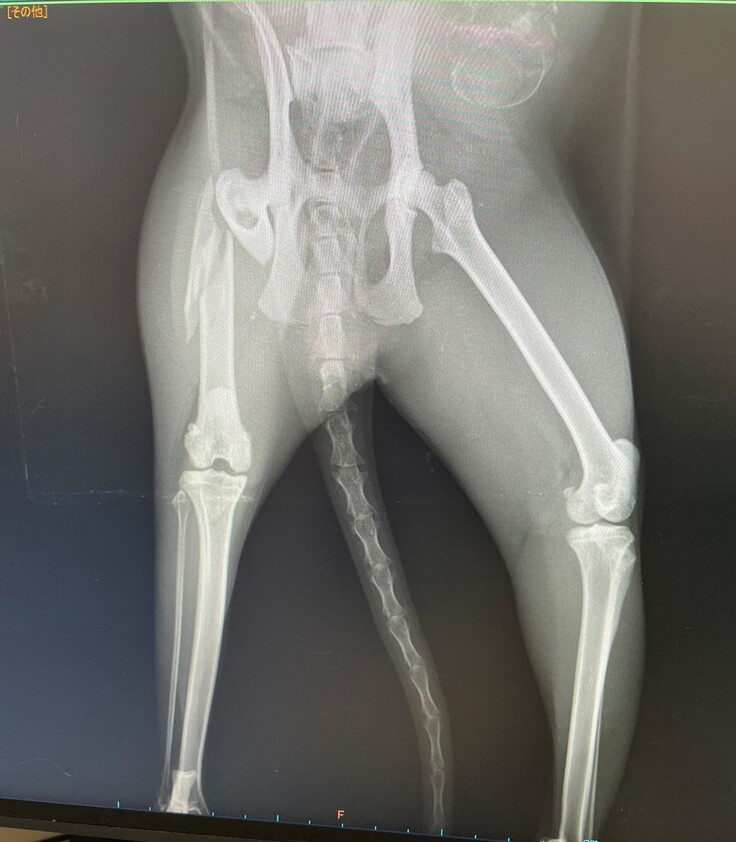

急いで病院へ連れて行ったところ・・・

先生「太ももの骨が3か所骨折してます。2か所は自然にくっつくと思いますが、

1か所は大きくずれて骨折している為自然にくっつくのが難しいと思います。」

と言われました。

先生「治す為には、手術が必要です。手術をしない選択をした場合、今後太ももから

骨折した骨が飛び出てくる可能性があります。」

●治療・手術内容

大腿骨の骨折3か所の手術、治療代。

妊娠している為、出産後に骨折の手術、体力回復後去勢手術を行う。